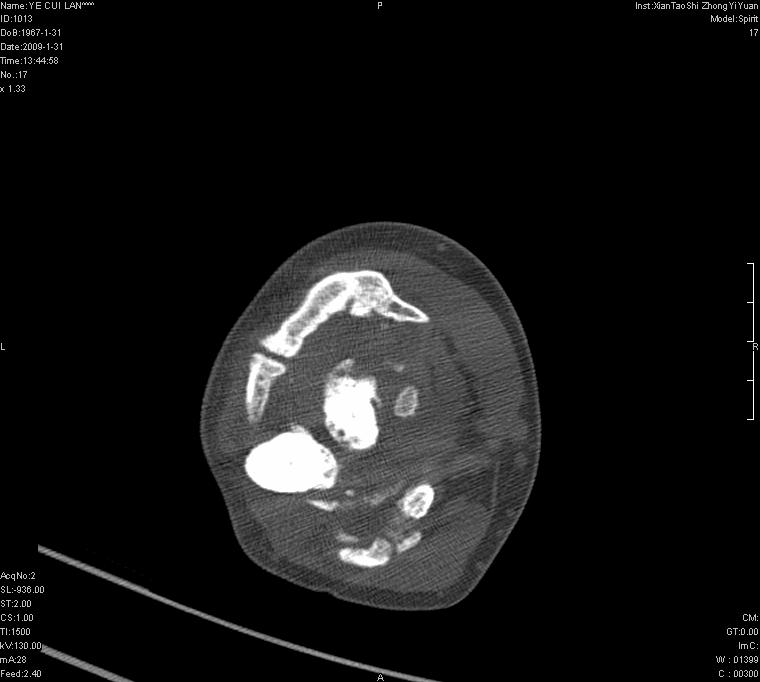

以下是引用王明发在2009-2-9 11:53:00的发言:[br]支持夏科氏关节,必要时行脊髓mri检查 [br]夏科氏关节是指由于某些神经系统疾病引起的关节病变,也被称为神经性关节炎。常见病因有脊髓痨、脊髓空洞症等。原发的神经病变可以造成关节深部感觉障碍,对于关节的震荡、磨损、挤压、劳倦不能察觉因而也不能自主地保护和避免,而神经营养障碍又可使修复能力低下,使病人在无感觉状态下造成了关节软骨的磨损和破坏,关节囊和韧带松弛无力,易形成关节脱位和连枷关节。关节面的破坏和骨赘的脱落变成关节内游离体。关节外形饱满肿胀,内有出血和渗出。这种病早期并无疼痛,不易被病人重视,仅表现为关节肿胀、无力、活动过度、动摇不稳。关节肿胀、无痛、活动范围超常是本病的重要特征。x光片可见有关节骨端广泛破坏、硬化或呈奇异形态,骨赘形成,关节间隙不规则或增宽,周围软组织钙化、关节内游离体、骨碎片等。结合x光片及临床症状,病人又有神经系统原发病症,即可确诊

以下是引用hhcckk在2009-2-9 14:31:00的发言:[br]夏科关节的六大表现[br]1.关节软组织肿胀。[br]2.关节的脱位与半脱位。[br]3.关节内的游离体。[br]4.关节面硬化,新骨形成。[br]5.骨质萎缩与破坏。[br]6.关节结构的紊乱。[br]加上患者无明显疼痛,诊断的把握性比较大